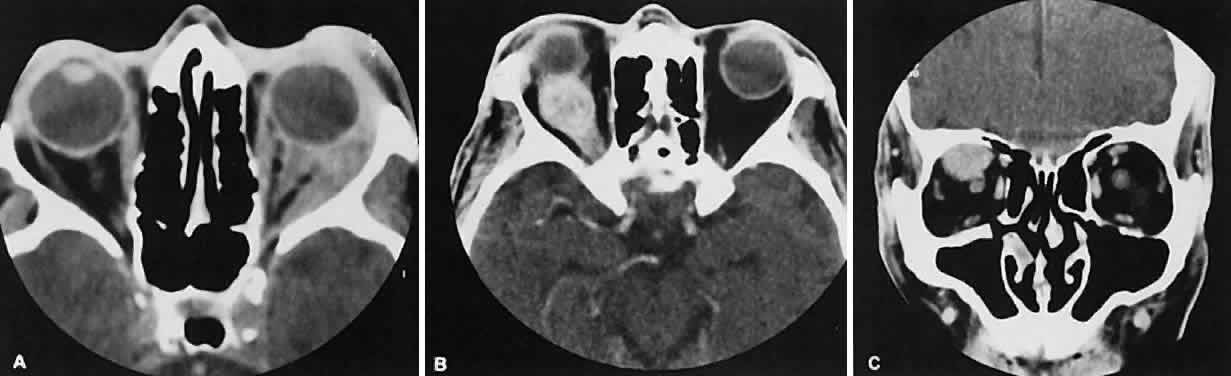

Fig. 7. Graves' orbitopathy with two variations. Axial (A) and coronal (B) views show symmetric fusiform enlargement of the extraocular muscles with tapered muscle insertions. Note the predominant enlargement of the inferior, medial, and superior rectus muscles with lesser involvement of the lateral rectus muscle, a frequent pattern of enlargement in Graves' orbitopathy. Axial (C) and coronal (D) views of Graves' orbitopathy with expansion of retrobulbar ground substance and relative sparing of the extraocular muscles.

Graves' orbitopathy probably represents the most frequent cause of proptosis and EOM enlargement. The CT findings are fairly stereotyped and typically display various degrees of EOM enlargement (Fig. 7). The inferior rectus muscle usually is affected earliest, followed by the medial rectus, superior rectus, and finally the lateral rectus muscle. Rootman and colleagues13 noted more frequent involvement of the superior rectus/levator and medial rectus muscles than what had been reported previously with Graves' orbitopathy. These muscles can be affected in isolation, with the exception of the lateral rectus. To the best of our knowledge, isolated lateral rectus enlargement has not been reported in Graves' orbitopathy and in our experience usually is associated with a sphenoid wing meningioma.

Morphologically, the EOM belly is enlarged, with a gradual tapering toward and sparing of the tendinous portion of the muscle. Tendon involvement is a typical feature of orbital myositis. Tendon involvement helps to differentiate this lesion from Graves' orbitopathy, although Rootman and Nugent43 have noted a rare patient with Graves' orbitopathy with this finding.

The muscle belly has a smooth contour with no edema of the adjacent orbital fat. We recently evaluated a patient with a referral diagnosis of Graves' orbitopathy. The patient was euthyroid but had severe orbital congestion typical of advanced Graves' orbitopathy. Imaging showed “dirty” orbital fat and lateral rectus muscle morphology that seemed atypical (Fig. 8). Biopsy specimen results showed a low-grade lymphoma. Hypertrophy of the medial rectus muscle can cause the medial wall to bow in toward the ethmoidal sinus from the chronic effects of pressure on the bone. The hypertrophied muscles also can give rise to a compressive optic neuropathy in the orbital apex as the enlarged muscles take their origin from the anulus of Zinn. Axial views of the apex show an apparent mass if the inferior rectus muscle is enlarged. It is imperative that additional views, sagittal or preferably coronal, be obtained to show the true nature of this apparent mass. Intracranial fat prolapse, seen by CT, may be another sign of optic neuropathy.44 An optic neuropathy also can be seen with relatively normal-sized EOM. An expanded fat compartment with optic nerve stretch has been associated with an optic neuropathy.45,46

Fig. 8. Low-grade lymphoma confined to orbit mistaken for Graves' ophthalmopathy in a 65-year-old man. A. On the axial view, orbital fat appears “dirty” with marked increase in soft tissue stranding. Muscles do not have a smooth appearance, lateral rectus muscles have lumpy appearance (arrow), and both lateral rectus muscles are disproportionately large for what typically is seen in Graves' orbitopathy. B. Coronal view also shows dirty orbital fat. Note left inferior rectus, which is small (arrowhead), and also is atypical in Graves' orbitopathy when there is enlargement of the other extraocular muscles.